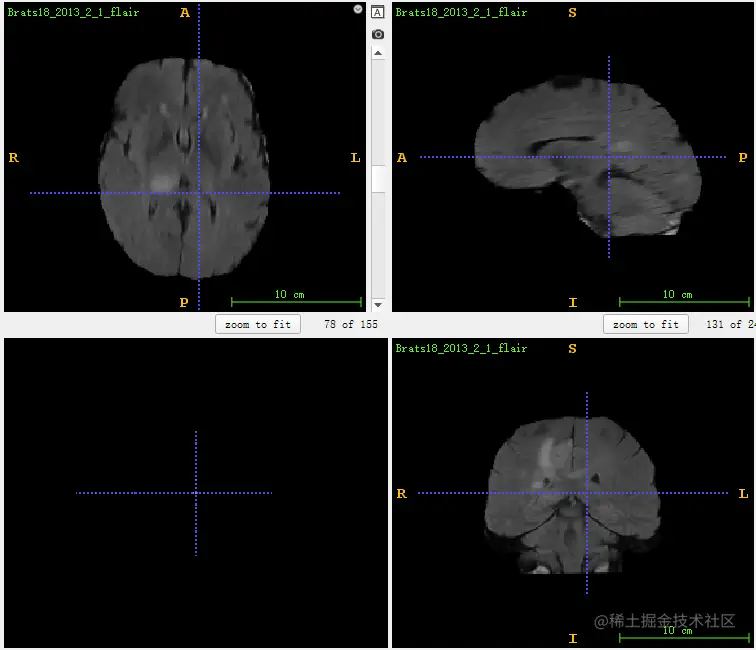

最后,总结论文的贡献,论文提出的这种方法是一种通用的配准方法,不仅适用于脑部的图像,而且对于肺部的医学图像同样适用。而且论文中提出的方法比原来的存在的方法更加的快速,即使在CPU上执行,速度比原来快了很多,说明该方法对于数据的处理能力非常有效,而且其dice的评分也相对较好。下面给出一组实验数据,如下,由于数据都为三维图像,而展示贴图时只能展示二维。

image.png